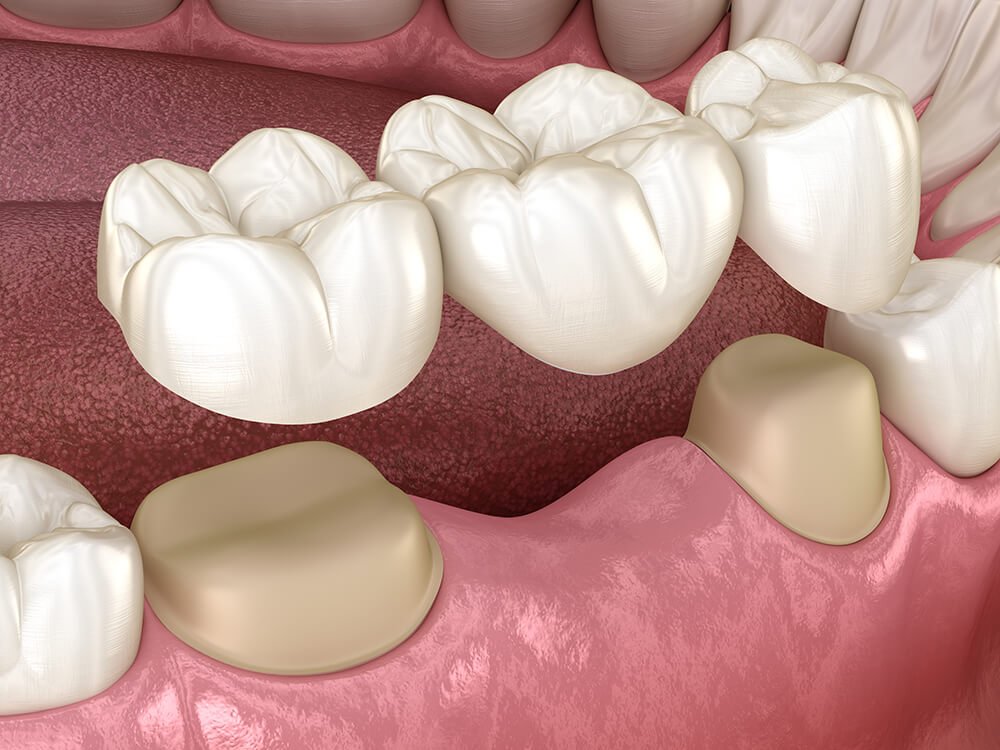

缺牙處前後牙狀況良好,可透過牙橋方式做假牙,若無鄰牙,則必須植牙;評估患者口腔狀況後,缺牙處植牙好處大於假牙時,同樣會建議植牙。當嚴重蛀牙、牙周病破壞厲害或牙齒斷裂,因而導致必須拔牙,形成缺牙時,患者通常也必須面臨做假牙或植牙的選擇。

固定假牙-牙橋